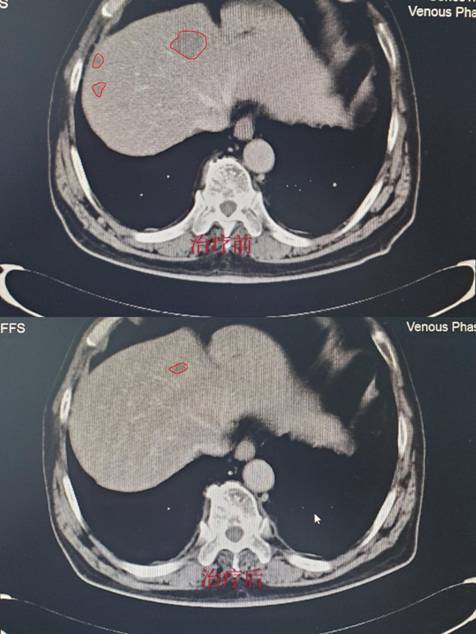

经过严格筛选,目前有一例72岁高龄患者顺利进入临床试验,入院诊断:肠癌伴肝肺广泛转移,经过3周期治疗后肝肺病灶明显缩小达60%,且治疗无明显毒副作用,患者及家属对我们的治疗表示非常满意。(CT结果如下,红色线框内为肿瘤组织。)